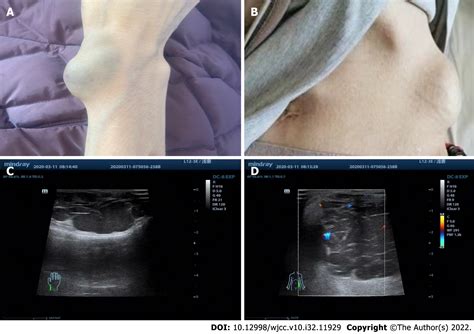

The primary symptom of a Blue Bleb Nevus is its distinctive appearance. These nevi are usually flat or slightly raised and have a blue or bluish-gray color. The blebs or blisters can be small or large and may rupture, leading to temporary changes in the appearance of the nevus. The nevi can occur anywhere on the body but are most commonly found on the trunk and extremities.

The diagnosis of a Blue Bleb Nevus is typically made through a clinical examination. A dermatologist will visually inspect the nevus and may use a dermatoscope to examine it more closely. A dermatoscope is a handheld device that magnifies the skin and allows the doctor to see the structure of the nevus in detail.